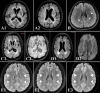

Figure 7.

Cases of different WML patterns and the characteristic CMBs in CSVD. Age-related WMLs (A1 and A2) mainly locate at periventricular areas, especially the frontal horns; a 14-year-old girl with refractory PFO-associated migraine was found with multiple subcortical spots asymmetrically surrounding bilateral WM areas (B, white arrows); symmetrical lesions around peri-basal ganglia and periventricular horns (C1) were found in an arteriosclerosis patient with deep CMBs (C2) in the basal ganglia; multiple subcortical lesions with an occipital dominance (D1) were identified in a CAA patient with lobar CMBs (D2); venous WMLs (E1-E3) are in a symmetrical and diffuse cloud-like pattern around bilateral periventricular areas (white triangles), and reversible in selected cases as ranged in severity from E1 to E3. Note: WML indicates white matter lesion; CMBs indicate cerebral microbleeds; CSVD indicates cerebral small vessel disease; PFO indicates patent foramen ovale; CAA indicates cerebral amyloid angiopathy.